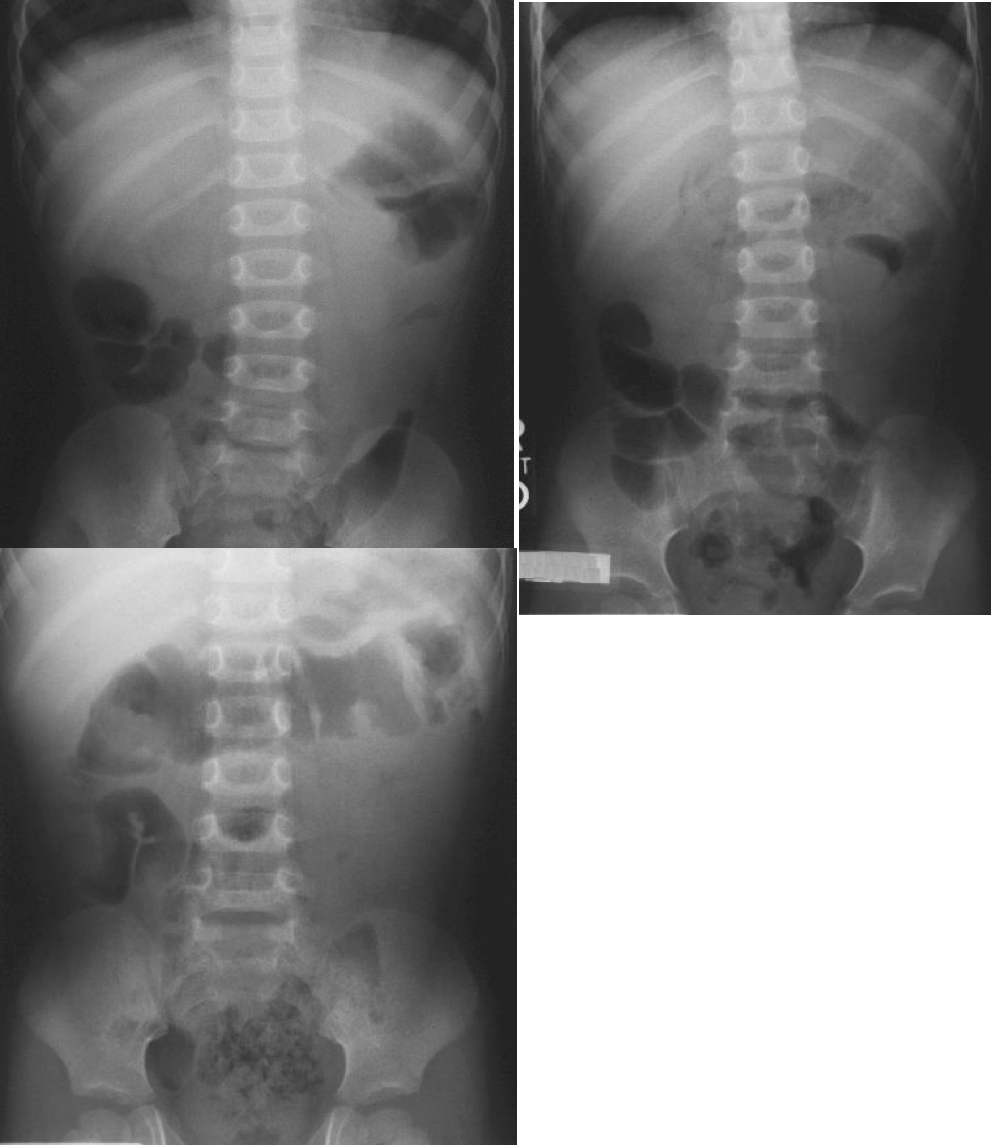

• Signs of intussusception on plain film:

• Target sign

• This radiograph shows a classic target sign in the right upper quadrant just below the liver. It resembles a chubby doughnut with a puffy center. It is very subtle. This radiograph also shows the absent liver edge sign and the crescent sign. A paucity of bowel gas is also noted.

• Crescent sign

• Soft-tissue density mass of the intussusceptum projecting into the colon (leading edge). If the head of the intussusceptum is projecting into a gas filled pocket, it will show itself. It often takes on a crescent shape; however, it may also merely resemble a protruding head into a gas filled pocket.

• This radiograph shows a classic crescent sign in the left upper quadrant. This radiograph indicates that the head of the intussuception is in the distal transverse colon. Also note that this radiograph demonstrates the target sign and the absent liver edge sign.

• This radiograph shows an atypical crescent sign in the right upper quadrant just below the liver. The head of the intussusception is coming up the ascending colon. It can be seen protruding upward into the gas filled transverse colon at the hepatic flexure.

• Absent liver edge sign

http: //www.hawaii.edu/medicine/pediatrics/pemxray/v1c02.html

• Target sign: Two approximately concentric circles of fat density to the right of the spine, due to layers of peritoneal fat surrounding and within the intussusceptum alternating with layers of mucosa and muscle. This sign resembles a very faint target, or bull’s eye, or doughnut appearance.

• Crescent sign: Soft-tissue density mass of the intussusceptum projecting into the colon (leading edge). If the head of the intussusceptum is projecting into a gas filled pocket, it will show itself. It often takes on a crescent shape; however, it may also merely resemble a protruding head into a gas filled pocket.

• Absent liver edge sign: loss of subhepatic angle

• Other non-specific

• Abdominal mass: An absence of bowel gas in the area suggesting indirectly that something is pushing normal bowel out of the way.

• Small bowel obstruction: Dilated bowel loops and air-fluid levels.